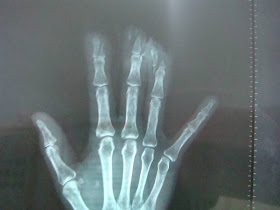

Finger Slices

The 63-year-old female patient had her fingers twisted into a machine.